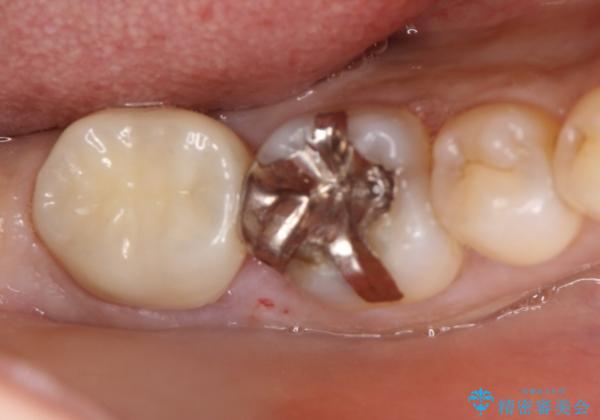

- 以前に他院で治療した被せものが外れたのを主訴に来院されました。

唾液から歯を守るため、ラバーダムシートを装着し古い材料を全て除去したうえで、う蝕を取り治療しました。

レントゲン写真から古い詰め物が神経と近接している事がわかります。万一に備え、ラバーダムシートを装着しながら治療を行いました。(万が一、虫歯の除去中に神経が露出した場合、神経を唾液から守るため。)